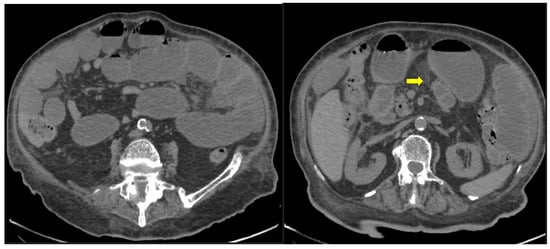

A single-center small retrospective study reported in COVID-19 patients 15 cases of acute aortic thrombosis, splenic artery thrombosis (associated with splenic infraction), superior mesenteric and renal artery thrombosis such as a celiac and an internal iliac thrombosis. An interesting part was a patient with infrarenal aortic wall inflammation and focal dissection, while many venous thromboses have been described (affecting the portal vein, inferior, superior mesenteric, renal, ovarian vein and inferior vena cava). Reports of indirect findings of the splanchnic branch venous occlusion described bowel wall severe edema, hyperenhancement or severe hypoenhancement, associated mesenteric and portal intravenous gas, bowel pneumatosis and pneumoperitoneum (Figure 10) [47]. Bari Dane et al. published a case of a simultaneous nonocclusive aortic, celiac and superior mesenteric artery thrombus combined with a complete common hepatic artery thrombus [48].

Figure 10. 56-year-old hospitalized male patient with COVID-19 pneumonia with raised level of d-dimers. CT depicting the thrombosed portal vein (yellow arrow). Note that in the same scan, there is extended small bowel thickening with mesenteric free fluid.